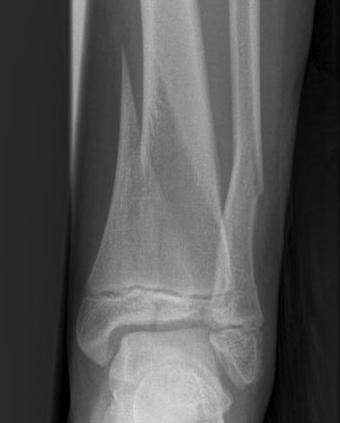

Triplanar Fracture

Definition

- fracture in coronal, sagittal and transverse planes

- 2, 3 or 4 part

Varieties

2 part

- can be medial or lateral based of site of main distal fragment

- typically anterolateral epiphysis attached to posterior metaphysis

- anteromedial intact distal tibia

3 part

- additional separate anterolateral epiphysis / Tillaux

Xray

Type III / Tillaux on AP

Type II on lateral

Management

ORIF

- > 2mm displacement

- usually anterolateral approach to reduce

- epiphyseal medial-lateral screw

- metaphyseal AP screw

Complications

Growth arrest 10%